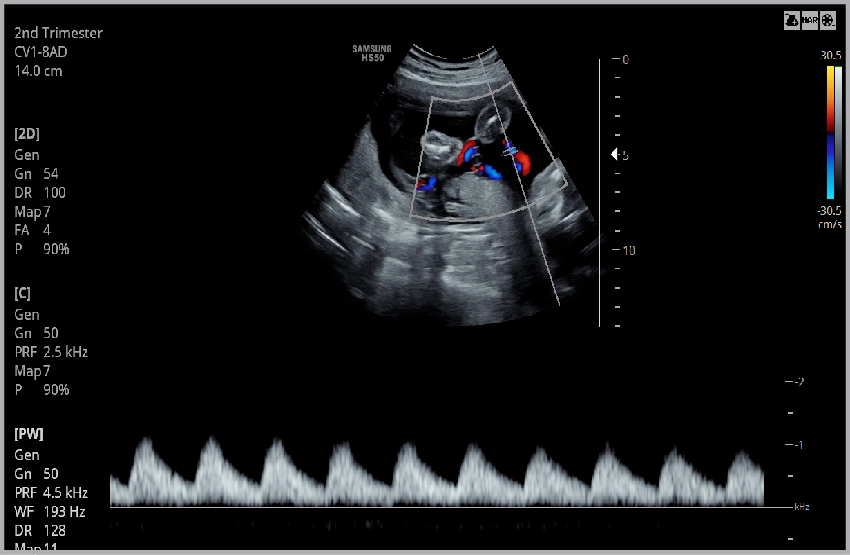

Пуповина в PW